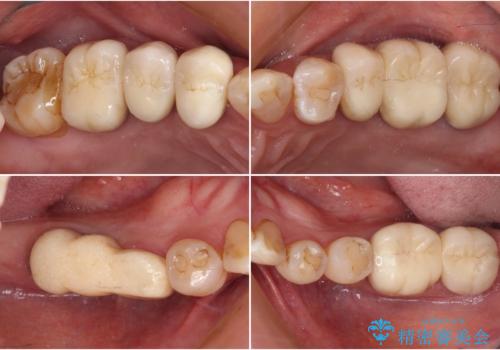

![[ 重度歯周病 ] 抜歯後のインプラント治療の症例 治療後](https://seimitsushinbi.jp/wp/wp-content/uploads/2023/09/e98e4e9cd9ff38fbf43e5e8e0214fa69-500x350.jpg?v=1695801055)